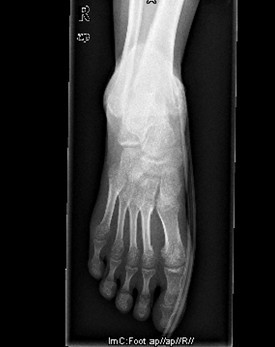

患者男,15岁,因“车祸致右足跟部皮肤撕脱伤清创缝合术后13天”入院。患者13天前因车祸导致右足疼痛流血伴功能障碍,右足跟部皮肤撕脱,遂到当地人民医院就诊,诊断为右跟骨骨折伴跟部皮肤严重剥脱伤,右胫骨远端骨折。急诊下行“右足跟部皮肤严重剥脱伤皮肤严重挫裂伤清创缝合术”。术后给予止痛、消肿、预防感染等对症处理,目前右足外侧及跟部皮肤变暗,坏死。患者为进一步诊疗,故转入我科继续治疗。

查体:右足内踝、外踝及跟部皮肤变暗,部分缺血坏死。未见畸形,稍肿胀。右足趾皮温无明显降低,右足趾感觉未见明显异常。右足内踝、外踝及跟部皮肤局部压痛。右踝关节活动受限,右踝关节活动诱发疼痛。右膝关节活动未见明显异常。 辅查:x片示右跟骨,右胫骨远端骨折。

诊断:1、右足清创缝合术后皮肤软组织坏死伴感染,2、右跟骨骨折,3、右胫骨远端骨折。 治疗:择期手术。